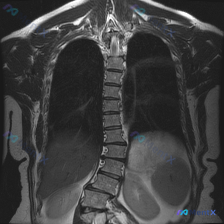

整理了一份病例影像资料,第一眼看到两个核心表现,有点纠结要不要用一元论串起来。 先放目前的影像发现: - 序列:胸腹部MRI-T2加权像冠状位 - 腹部:左肾区域可见多发、大小不等的圆形高信号囊性病灶,边界清晰,内部信号均匀,正常肾实质受压变薄,左肾整体轮廓增大;右肾(图像左侧)信号大致均匀;肝脾未...

今天看到一份很有意思的影像资料,标记的观察焦点是“脾脏病变”,但仔细读完完整MRI分析后,发现整个诊断方向完全不在脾脏上,整理一下思路分享给大家。 先看完整的影像事实 这是一份冠状位腹部MRI(T2加权序列)的分析: - 肝脏:形态轮廓尚可,肝实质内见多发圆形/类圆形极高T2信号灶,边界清晰,符合液...